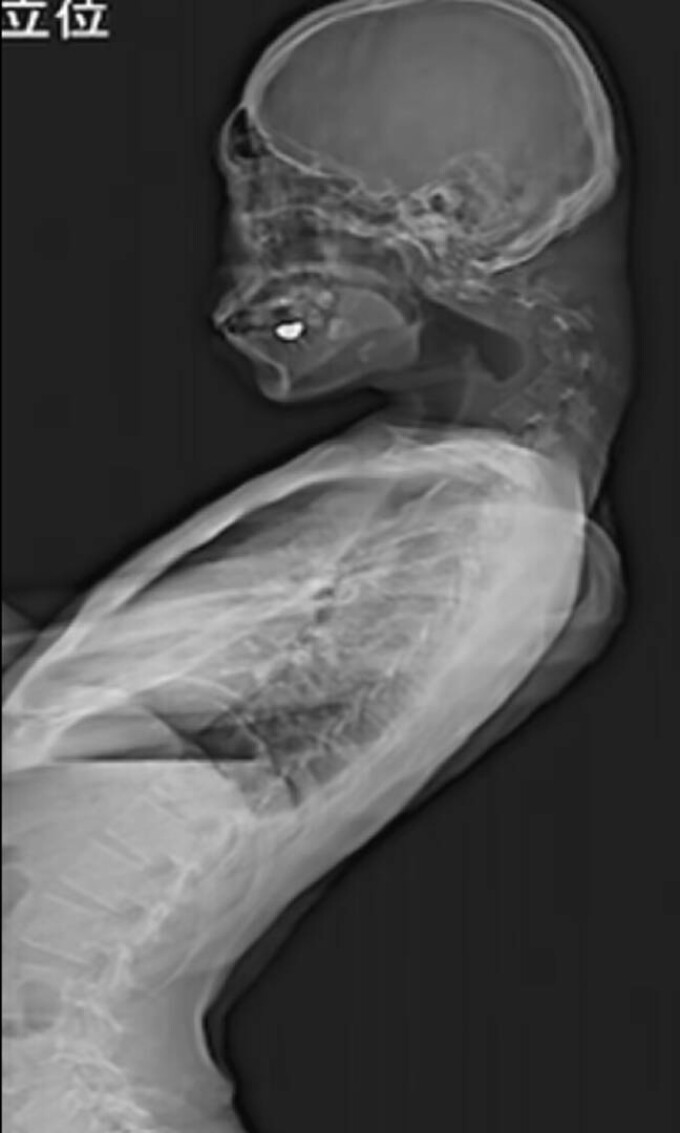

Potrivit unui raport publicat în JOS Case Reports, pacientul s-a prezentat la spital cu dureri intense de gât care persistau de peste șase luni. În cele din urmă, nu a mai putut să-și susțină capul, iar dificultățile de înghițire și pierderea în greutate au accentuat gravitatea situației. Radiografiile și investigațiile detaliate au relevat deformări ale vertebrelor cervicale și acumularea de țesut fibros, cauzate de o postură incorectă menținută pe termen lung.

Imagini cu coloana deformată a tânărului / Sursa foto - sciencedirect.com